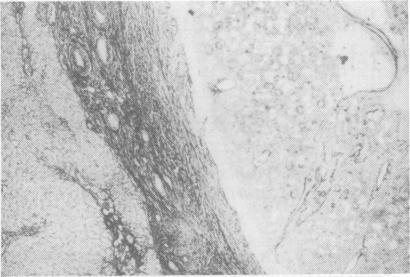

A case of recurrent hepatocellular carcinoma following resection is reported. The patient received 2 treatments of 131I-lipiodol administered via the hepatic artery at angiography. Good localization in tumour tissue was observed on subsequent computed tomographic scans and no adverse effects were seen after either treatment. After the first treatment 2 nodules of recurrent tumour were resected and proved to be totally necrotic. The patient remains well 9 months later with a persistently elevated serum alphafetoprotein but no evidence of residual tumour. It is suggested that 131I-lipiodol may be the treatment of choice for small tumours in elderly high-risk patients.

本文报告了1例肝癌切除术后复发的病例。该患者在血管造影时经肝动脉接受了2次131I-碘油治疗。在随后的计算机断层扫描中观察到肿瘤组织有良好的定位,且每次治疗后均未出现不良反应。第一次治疗后,切除了2个复发性肿瘤结节,病理证实完全坏死。9个月后患者情况良好,血清甲胎蛋白持续升高,但无残留肿瘤迹象。提示131I-碘油可能是老年高危患者小肿瘤的首选治疗方法。